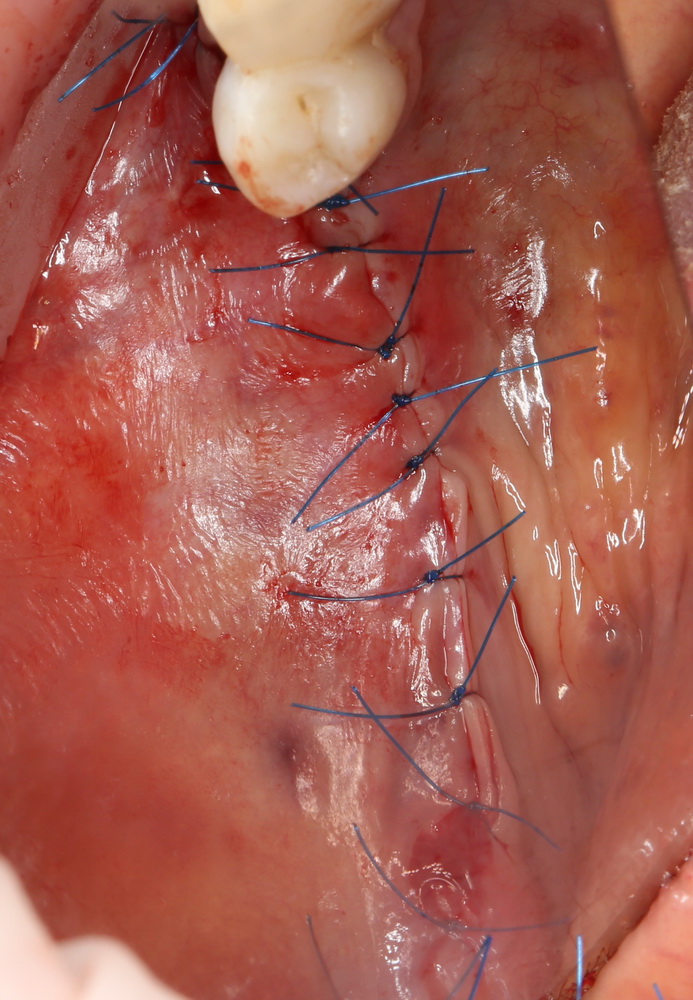

и теперь швы. Наглухо (Фактор II):

Вот так мы сочетаем имплантацию с остеопластикой. И, если мы сделали все по правилам и без противоречий здравому смыслу, то через 3 месяца мы должны получить неплохой результат.

Пока же мой ортопед Ахинян Давид заменил съемный протез, который, кстати, уже не одевался из-за изменения формы протезного ложа, на временную несъемную конструкцию. Очень важно, чтобы в процессе интеграции импланта и регенерации графта, на него ничто не давило.

Через 3 месяца мы готовы приступить к формированию десны. И каким-то невероятным образом, у нас получился даже избыток слизистой оболочки. Что, безусловно, очень даже хорошо:

По фотографии хорошо видно, как изменилась форма альвеолярного гребня после операции.